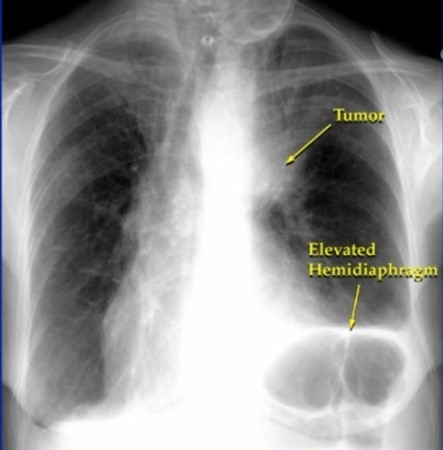

안녕하세요! 오늘은 폐렴의 초기 증상에 대해 알아보려고 합니다. 갑자기 기침이 심해지거나 숨이 차는 등 평소와 다른 호흡의 변화가 있을 때, 그 증상이 단순한 감기인지 아니면 폐렴으로 이어지는 문제인지를 구분하는 것이 중요합니다. 폐렴은 빠르게 진행될 수 있기 때문에, 초기 증상에 대한 인식을 높이는 것이 예방과 치료에 큰 도움이 됩니다.

폐렴은 조기에 치료하면 완치가 가능하지만, 늦으면 합병증이 발생할 수 있으므로 증상이 나타나면 즉시 의료기관을 방문하는 것이 중요합니다.

폐렴의 초기 증상을 잘 알고 있다면, 더 빠르게 적절한 조치를 취할 수 있습니다. 만약 자신이나 주변에 폐렴 의심 증상이 나타난다면, 지체하지 말고 병원을 방문해 꼭 진료를 받으세요. 건강은 무엇보다 중요하니까요! 이번 글이 도움이 되셨기를 바랍니다. 감사합니다.